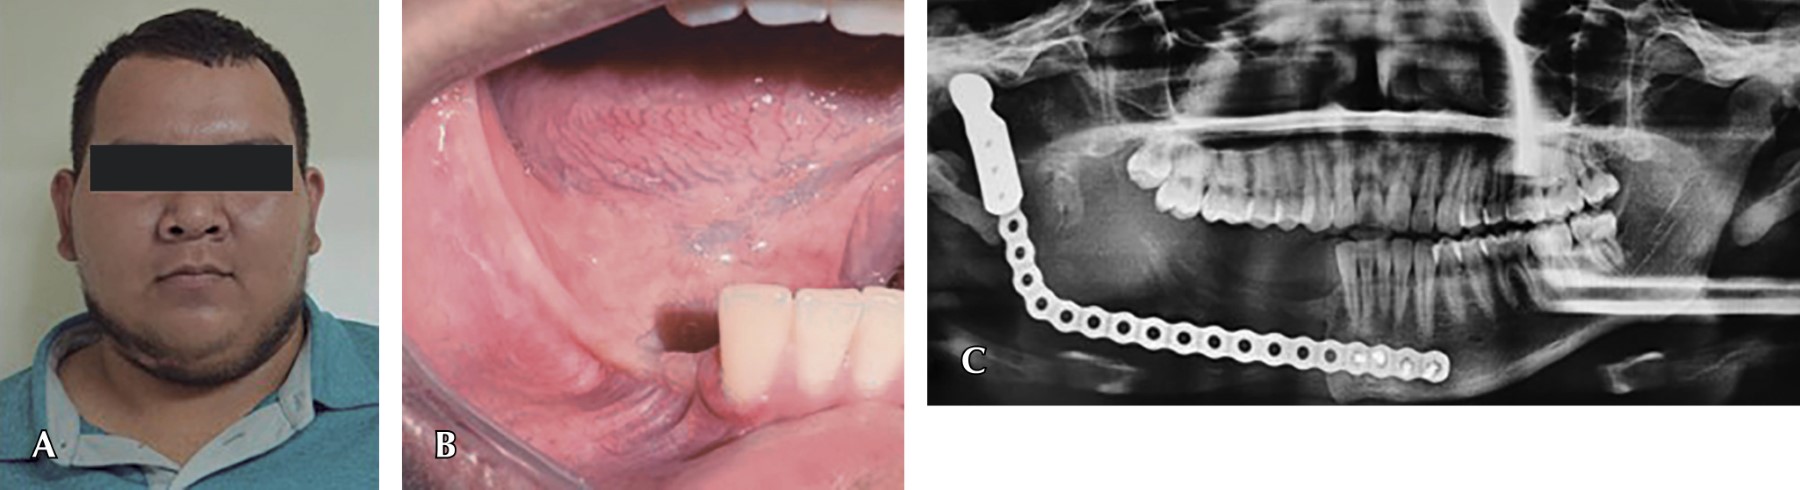

Paciente masculino de 17 años de edad, se presenta a consulta de primera vez contando ya con diagnóstico histopatológico de ameloblastoma plexiforme. El paciente no cuenta con antecedentes de relevancia para su padecimiento actual. A la exploración física muestra asimetría facial a expensas de un aumento de volumen en la región de ángulo y rama mandibular del lado derecho (Figura 1A) con seis meses de evolución, la piel se muestra lisa, eutérmica e isocrómica a los tejidos adyacentes. La tumefacción es indurada a la palpación y con dolor moderado a la digitopresión. En la exploración intraoral se observa una mucosa sin alteraciones en color, expansión de la cortical bucal, así como la obliteración del pliegue mucogingival en la región molar del mismo lado y destaca la salida de material purulento a través del sitio donde se tomó previamente la biopsia (zona retromolar) (Figura 1B), el resto de estructuras sin alteración.

Cuenta con estudio radiográfico tipo ortopantomografía, en la cual se observa una lesión osteolítica radiolúcida multilocular bien delimitada, con bordes aparentemente escleróticos, misma que abarca desde la porción mesial del diente 46 hasta la región subcondílea ipsilateral, causando deformación de la basal mandibular y rizólisis del 47 (Figura 1C).

Figura 1